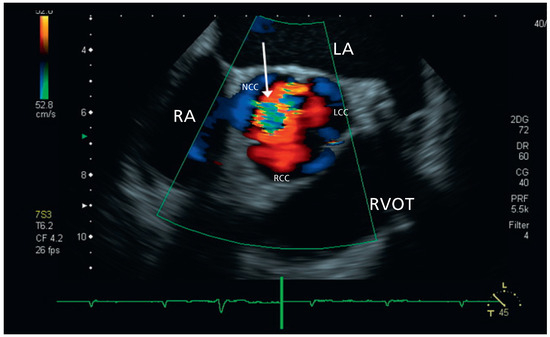

Aortic Valve Rupture Due to a Motorcycle Accident

by Daniela Vocke, Igal Moarof, Peter Matt and Pablo Anabitarte

Cardiovasc. Med. 2011, 14(6), 192; https://doi.org/10.4414/cvm.2011.01597 - 29 Jun 2011

A 62-year-old male patient was admitted as a result of a motorcycle accident [...] Full article